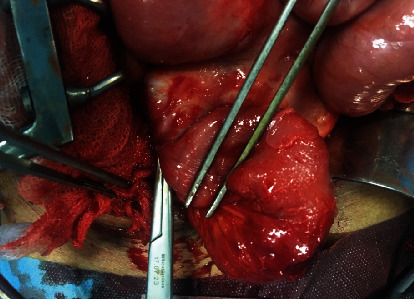

Sclerosing encapsulating peritonitis (SEP) is an unusual fibroinflammatory disease of the peritoneum marked by the development of a fibrous membrane enveloping generally the small intestines. The knowledge around this subject is not completely understood. And the etiology can be either idiopathic or secondary to several diseases, treatments, and/or medications. We present a case of a 52-year-old man suffering from atypical clinical symptoms including recurrent abdominal ascites and intestinal obstruction. An abdominal computed tomography showed findings typical of SEP. Therefore, the patient benefited from exploratory laparotomy, which confirmed the diagnosis of idiopathic SEP. Postoperatively, he again had an episode of bowel obstruction, but this was controlled with steroids. Diagnosis of SEP is a real challenge to surgeons, gastroenterologists, and radiologists. And imagery is very helpful to make the diagnosis. Consequently, it is imperative that all hospital practitioners should distinguish between this lesion and other etiology of acute peritonitis.

Abstract Image